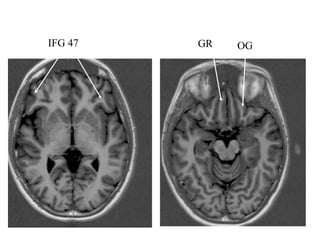

• IFG (44(opercularis) 45(triangularis) 47 (orbitalis)

IFG- 44 IFG- 45

IFG 47 GR OG